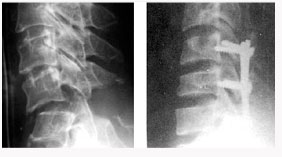

척추관 협착증의 방사선 소견

후방 요추체간 유합술 (PLIF) : 광범위한 후방 감압술 후 추간판(디스크)을 제거한 후 골이식을 시행하여 추체간 유합을 얻는 것

- 후외방 유합술에 비해 절개가 적다

- 신경근에 대한 충분한 감압이 이루어진다

- 추간판(디스크)로 인한 동통 및 재발이 없다

- 추간판 높이를 정상으로 회복시켜 준다

- 척추 정렬을 정상으로 회복시켜 준다